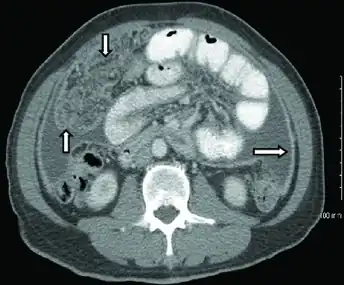

CT scan of peritoneal tuberculosis, a form of extrapulmonary tuberculosis. The omentum and peritoneal surfaces are thickened (arrows).<ref name="AkceBonner2014">Akce M, Bonner S, Liu E, Daniel R (2014). "Peritoneal tuberculosis mimicking peritoneal carcinomatosis". Case Reports in Medicine. 2014: 436568. doi:10.1155/2014/436568. PMC 3970461. PMID 24715911.

In active pulmonary TB, infiltrates or consolidations and/or cavities are often seen in the upper lungs with or without mediastinal or hilar lymphadenopathy or pleural effusions ( tuberculous pleurisy). However, lesions may appear anywhere in the lungs. In disseminated TB a pattern of many tiny nodules throughout the lung fields is common - the so-called miliary TB. In HIV and other immunosuppressed persons, any abnormality may indicate TB or the chest X-ray may even appear entirely normal.

Abnormalities on chest radiographs may be suggestive of, but are not necessarily diagnostic of, TB. However, chest radiographs may be used to rule out the possibility of pulmonary TB in a person who has a positive reaction to the tuberculin skin test and no symptoms of the disease.

Cavitation or consolidation of the apexes of the upper lobes of the lung or the tree-in-bud sign[7] may be visible on an affected patient's chest X-ray.[1] The tree-in-bud sign may appear on the chest CTs of some patients affected by tuberculosis, but it is not specific to tuberculosis.[7]